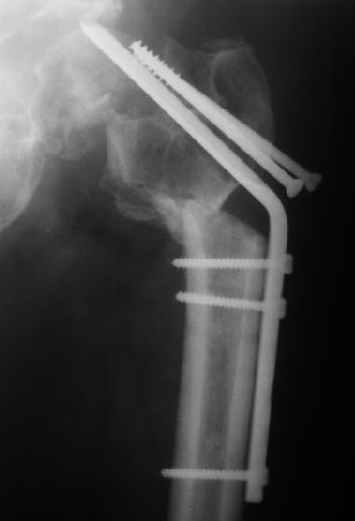

Мужчину 56 лет оперировали у нас в августе 2003 г. - вальгизируюшая остеотомия из-за позднего (через 2 мес. после травмы) поступления с переломом шейки бедра (картинки 1,2). Курильщик, соматической патологии не было. Сейчас поступил с жалобами на проблемы в области тазобедренного сустава, на снимках 3,4 видно вырезывание клинка.

Чтоб можно посоветовать в этой ситуации? Заранее спасибо.

Now he re-admitted with the images 3,4.

What would you do in the situation?